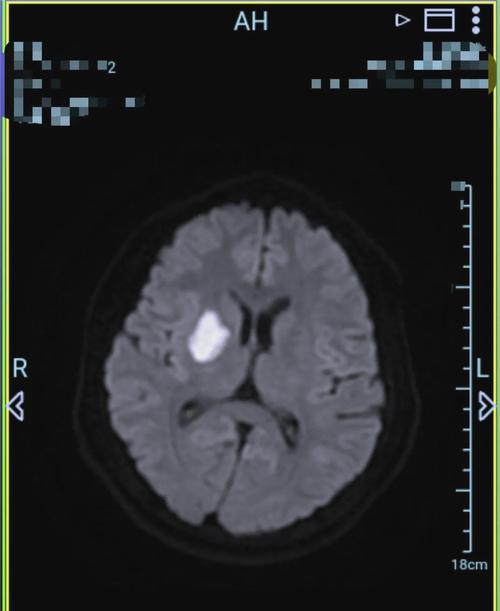

(图片来源网络,侵删)- 早期发现: 对于急性缺血性脑梗,MRI可以在发病后的几分钟到几小时内就发现异常信号,特别是DWI(弥散加权成像)序列,对早期脑梗死的诊断非常敏感,几乎在细胞水肿出现的第一时间就能捕捉到。

- CT检查的短板: 相比之下,普通CT在脑梗发病后的6小时内往往难以发现明确的梗死灶,只有在发病24-48小时后,当脑组织发生明显坏死时,CT才能显示出低密度灶。